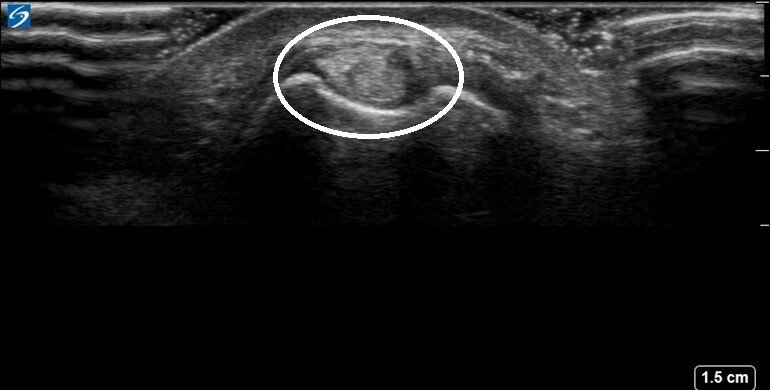

Wrist Compartment Six Image

Circled: Extensor Carpi Ulnaris